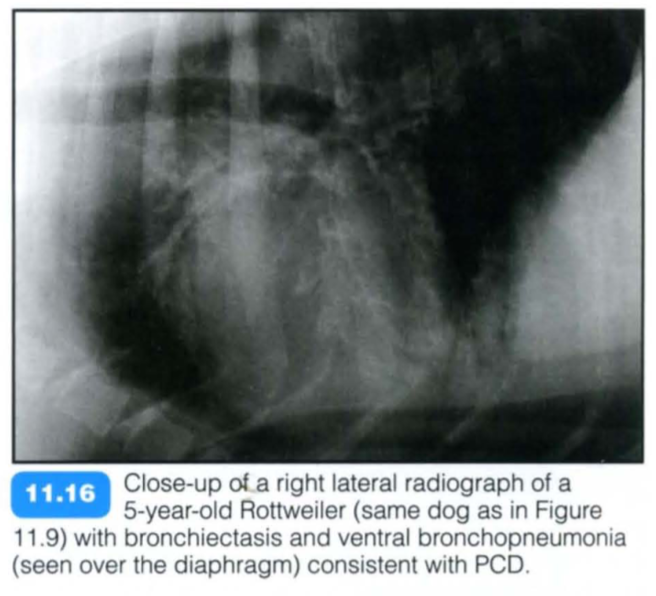

Primary ciliary dyskinesia (PCD), also known as immotile cilia syndrome, is a diverse group of inherited structural and functional abnormalities of the respiratory and other cilia, which results in recurrent respiratory tract infections in the dog. More specifically, PCD is an inherited defect in microtubule formation, affecting cilia of the respiratory and urogenital tract and the auditory canal.

Typically PCD is diagnosed in young purebred animals with a reported higher incidence in the Bichon Frise. The condition may be seen in mixed breed dogs and also in cats.

There is a relatively high prevalence of a respiratory disease and the phenotype is almost identical to PCD in humans. The respiratory manifestations include chronic rhinitis , bronchitis and severe pneumonia with or without bronchiectasis. Affected animals are presented with recurrent chronic nasal discharge, productive cough, respiratory distress and exercise intolerance. Additional findings are infertility, hydrocephalus and loss of hearing.

Radiography: